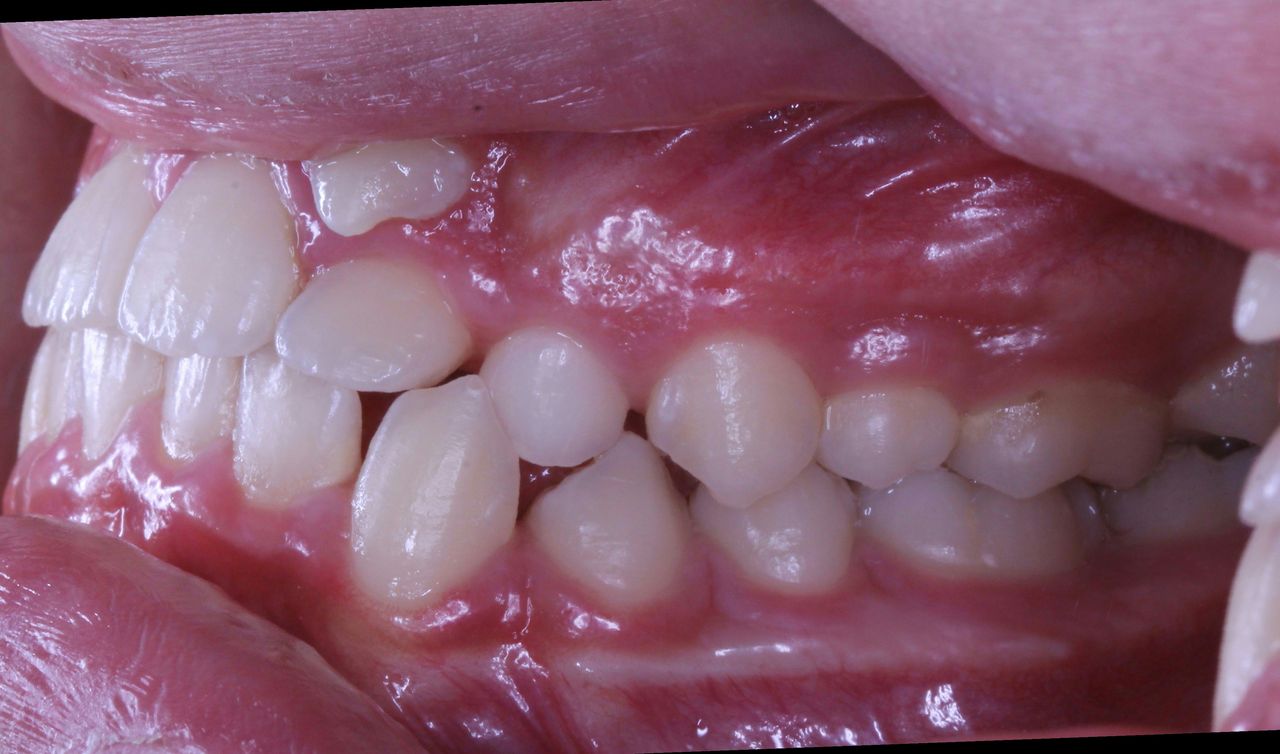

それでは治療開始前の状態です

このように1番目と2番目の歯の間から犬歯3番目の歯が生えてきました。

また乳歯Cが残っているので 歯の順番でいうと

132Cという順番になっております

それを

132Cから Cを抜歯して 123という順番に並べなおすのです